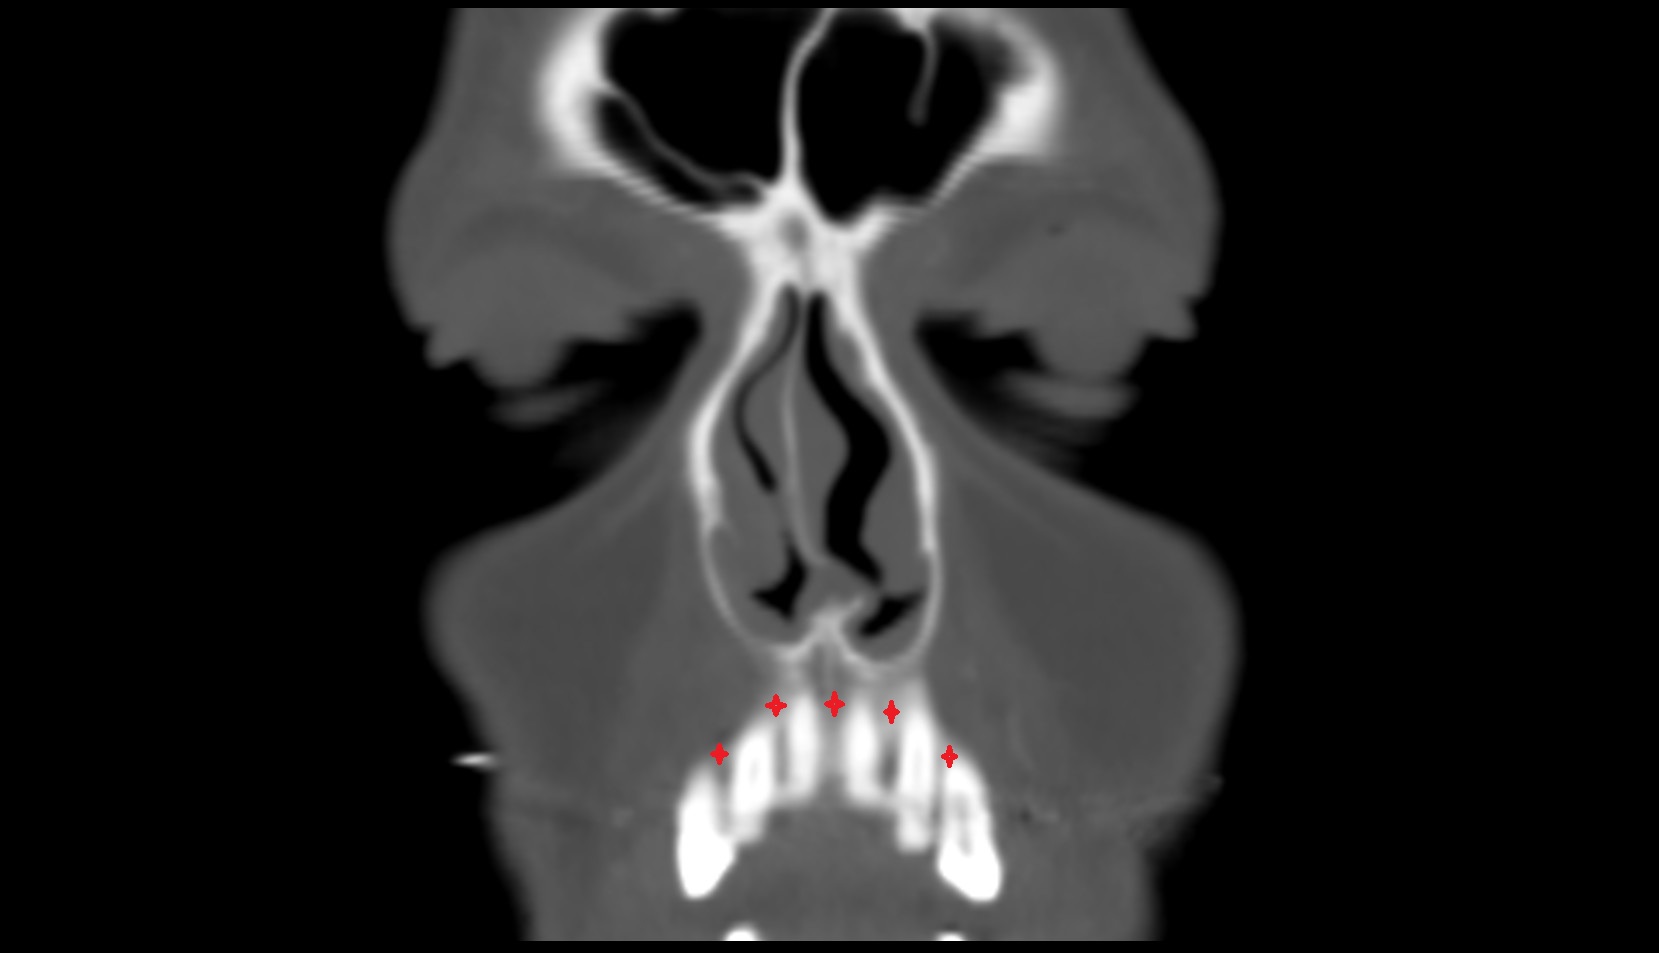

- Central inferior incisor tooth

- Central superior incisor tooth

- Inferior canine tooth

- Lateral inferior incisor tooth

- Lateral superior incisor tooth

- superior canine tooth

- Superior first molar tooth

- Superior first premolar tooth

- Superior second molar tooth

- Superior second premolar tooth

- Superior third molar tooth

- Maxillary sinus

- Nasal septum